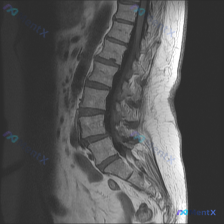

整理到一份影像资料,有点意思: 只有腰椎MRI T1加权矢状位,能看到: 1. 腰椎生理前凸存在,但L5/S1有明显的腰椎滑脱(L5相对于S1向前移位) 2. 下腰椎多个椎间盘信号减低、L4/L5和L5/S1椎间隙变窄 3. 对应节段终板有Modic II型改变(脂肪化) 4. L4/L5及L5/S...